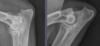

Q

Left: immature; more faint

Right: mature; more opaque